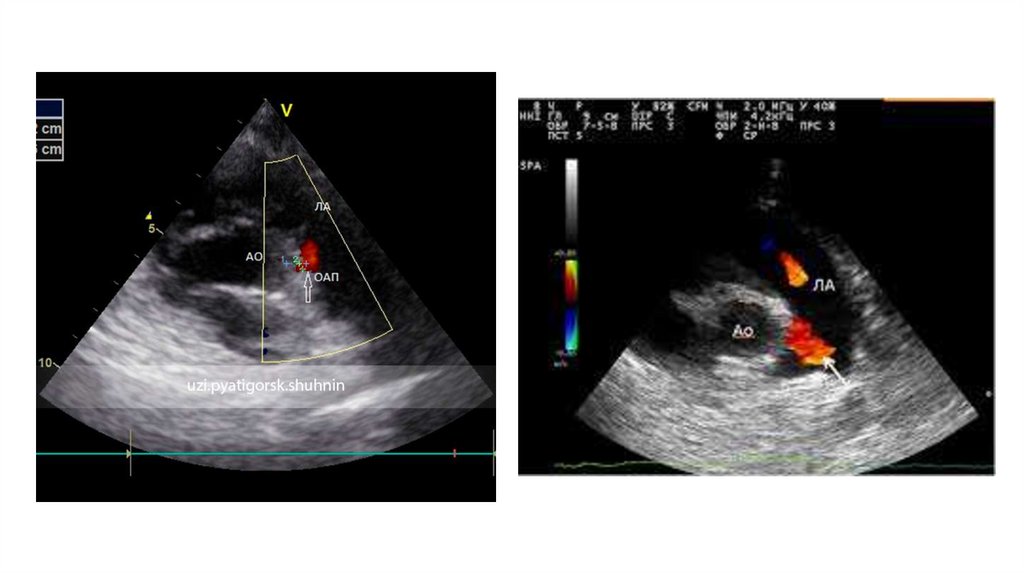

7.  Инструментальная диагностика

Инструментальная диагностика

• ЭхоКГ – золотой стандарт. Ключевые задачи:

1.Визуализация протока: Доступы – высокий парастернальный по короткой

оси, супрастернальный.

2.Измерение диаметра: В В-режиме или ЦДК в самом узком месте.

3.Оценка сброса: ЦДК и спектральный допплер (непрерывный

турбулентный поток).

4.Оценка гемодинамической значимости:

1. Легочная гиперперфузия: Размер ЛП (ЛП/Ао > 1.4-1.5), размер ЛЖ

(КДР ЛЖ).

2. Системная гипоперфузия: Оценка диастолического кровотока в

нисходящей/брюшной аорте (антеградный/нулевой/ретроградный).

5.Исключение сочетанной патологии: Коарктации аорты, других ВПС.